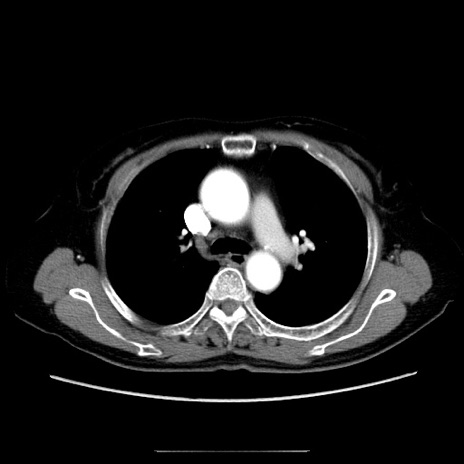

冠状断像

【症例】70歳代女性

【主訴】お腹が張る

【現病歴】1週間くらい前から腹部膨満の自覚あり。昨日夜から増悪したため、本日救急外来受診。

【身体所見】意識清明、BT 36.5℃、BP 165/106mmHg、HR 80bpm、SpO2 98%、腹部:膨満、軟、自発痛・圧痛なし、触診にて不快感あり、腸蠕動音:減弱

【データ】WBC 12600、CRP 1.04